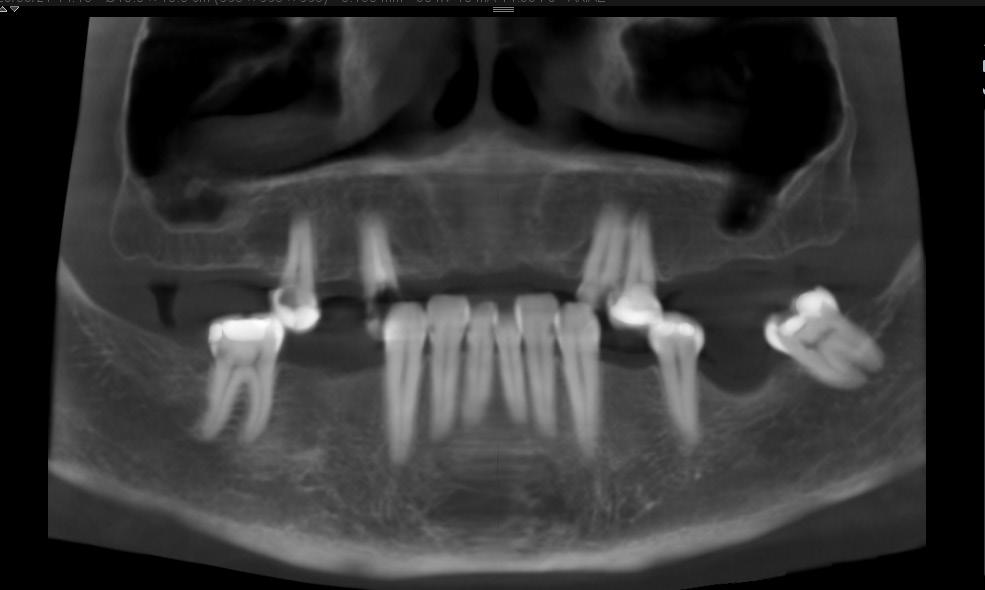

DISCUSIÓN

Tomando en cuenta nuestro caso clínico, los estudios histopatológicos determinaron que estamos frente a un proceso inflamatorio crónico inespecífico con fibrosis marcada, su extirpación fue exitosa sin ningún tipo de complicaciones dentro de la cirugía y del postoperatorio; Zambuzzi et al reportaron en un estudio que la hidroxiapatita natural de hueso bovino promueve un ambiente adecuado para la adhesión, proliferación y diferenciación de osteoblastos, lo cual lleva a una adecuada resolución del hueso (3); desde otro ángulo Chiapasco A. et al comparan la regeneración de cavidades quísticas mediante esponjas de colágeno (mantenedoras del espacio y estabilizadoras) y hueso liofilizado desmineralizado de cadáver; no encontraron diferencias estadísticamente significativas entre ambos grupos a los dos años, lo que confirma que en cualquier caso se presentará buena cicatrización ósea posterior a la quistectomías, al utilizar materiales aloplásticos, injertos o la propia formación ósea espontánea; ambos procedimiento utilizados en nuestro paciente (4).

RIIS UNIVALLE. Jul-Dic. 17(43), 2022; ISSN: 2075-6208 105 Aplicación de biomateriales post exeresis en un quiste inflamatorio radicular Adrián-Hurtado y cols.

Figura 9. Obtención del Sticky bone (SB), mezcla del A- PRF más el hueso bovino.

Hernández R. et al concuerdan con que el uso de injertos óseos es un método seguro, simple, eficaz y que además el odontólogo puede emplear para diversos defectos óseos alveolares, siempre y cuando sea considerado su sitio de colocación ya que esto influye directamente con el éxito del tratamiento. En sus tres reportes de casos pudo evidenciar que el uso de injertos promovió su buena oseointegración y presentó un alto nivel de biocompatibilidad, además ninguno de estos tres autores difiere en sus opiniones (5) (9) (10).

Cuando existe pérdida de tejido óseo extenso es importante utilizar biomateriales que produzcan osteoconducción, osteoinducción y osteogénesis, puesto que estos tienen la capacidad de estimular

REFERENCIAS BIBLIOGRÁFICAS

la formación ósea de una manera más rápida; dependiendo del tipo de material veremos que la formación ósea será más adecuada, tanto en volumen como en calidad; con esto no tratamos de indicar que la recuperación fisiológica no será buena, sino que esta tarda más tiempo, en contraste con el uso biomateriales y el aumento de densidad ósea; debido a la extensión de la cavidad, el relleno de la misma con el Sticky bone y cubrir con una membrana de pericardio porcino, se espera que cumplan la función osteoconductora en la cavidad. Basándonos en los estudios y revisiones recientes, esperamos buenos resultados en nuestros pacientes, debido a que el tiempo de neoformación dura aproximadamente 6 a 8 meses, por lo cual aún se encuentra en proceso.

1. García, A., Buljadón, A., & Rodríguez, A. (Febrero de 2015). Lesiones periapicales. Diagnóstico y Tratamiento. Avances en Odontoestomatología, XXXI(1), 31-42. Recuperado el 9 de Juio de 2018, Doi: https://doi.org/10.4321/S0213-12852015000100005

2. Swennen G, Dempf R, Schliephake H. Cranio-facial distraction osteogenesis: a review of the literature. Part II: Experimental studies. Int J Oral Maxillofac Surg. 2002 Apr; 31(2): 123-35. doi: https://doi.org/10.1054/ijom.2002.0225

3. Rebolledo M, Harris J, Higgins E, Molinares L. Cicatrización y regeneración ósea de los maxilares después de una quistectomía: reporte de un caso y revisión de la literatura. Univ Odontol. 2011 Jul-Dic; 30(65): 71-78 Recibido para publicación: 15-05-2011 Correcciones recibidas: 09-09-2011 Aceptado para publicación: 11-10-2011 Disponible en http://www.javeriana.edu.co/

4. Zambuzzi WF, Ferreira CV, Granjeiro JM, Aoyama H. Biological behavior of pre-osteoblasts on natural hydroxyapatite: a study of signaling molecules from attachment to differentiation. J Biomed Mater Res. 2011 May; 97(2): 193-200. Epub 2011 Mar 10. Doi.10.1002/jbm.a.32933 https://doi. org/10.1002/jbm.a.32933

5. Chiapasco M, RossiA, Motta JJ, Crescentini M. Spontaneous bone regeneration after enucleation of large mandibular cysts: a radiographic computed analysis of 27 consecutive cases. J Oral Maxillofac Surg. 2000 Sep; 58 (9): 942-8. Discussion 949. Doi https://doi.org/10.1053/joms.2000.8732

6. Edgar Eduardo Serrano Mejía Trabajo de grado para otorgar el título de Odontólogo Director Nohora Camila Rúgeles Páez Esp. Implantología oral y reconstructiva Universidad Santo Tomás, Bucaramanga División de Ciencias de la Salud Faculta de Odontología 2020. http://hdl.handle. net/11634/20496

7. Block MS. The processing of xenografts will result in different clinical responses. Journal of Oral and Maxillofacial Surgery 2018. Doi. 10.1016/j.joms.2018.10.004

8. Johnson, B., Fayad, M., & Witherspoon, D. (2011). Cirugía Perirradicular. En K. Hargreaves, & S. Cohen, Vías de la pulpa (págs. 720-755). Barcelona, España: Elsevier Mosby. Doi. https://doi. org/10.1016/B978-0-323-06489-7.00021-7

9. Morales, D., & Vila, D. (2016). Regeneración ósea guiada en Estomatología. Revista Cubana de Estomatología, LIII(1), 67-83. Recuperado el 17 de Julio de 2018, de http://scielo.sld.cu/scielo. php?script=sci_arttext&pid=S0034-75072016000100008

10. Rebolledo, M., Harris, J., Higgins, E., & Molinares, L. (2011). Cicatrización y regeneración ósea de los maxilares después de una quistectomía: reporte de caso y revisión de la literatura. Universitas Odontológica, 30(65), 71-78. Obtenido de http://www.javeriana.edu.co/universitasodontologica

RIIS UNIVALLE. Jul-Dic. 17(43), 2022; ISSN: 2075-6208 106 Aplicación de biomateriales post exeresis en un quiste inflamatorio radicular Adrián-Hurtado y cols.

DOI: https://doi.org/10.52428/20756208.v17i43.390

Inclusión dentaria por un odontoma compuesto

Dental inclusion by a compound odontoma

Javier Adrian Burgos 1. Francis Daniela Argandoña Ortiz2. Gabriela Adriana Lara León3

1Medico cirujano, Cirujano Dentista, Esp. En Cirugía Bucal, Msc. En Implantología Oral, Docente Univalle Sub- Sede La Paz jadrianb@univalle.edu

2 Estudiante de la Carrera de Odontología, Universidad Privada del Valle La Paz, aof2015031@est.univalle.edu